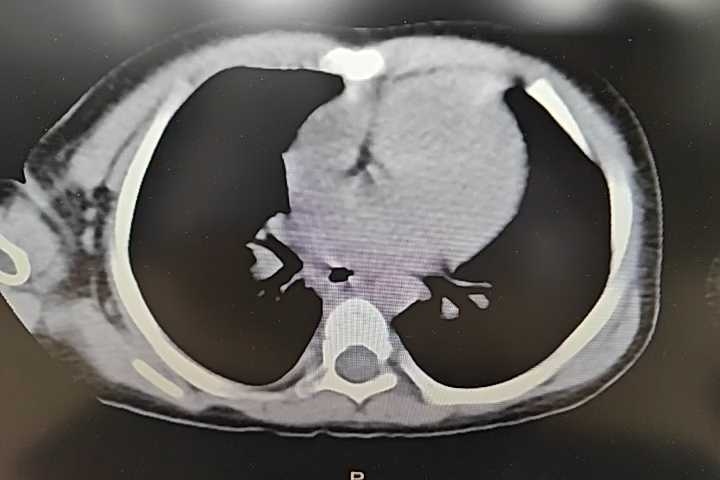

入院后影像学如下:

腹部CT